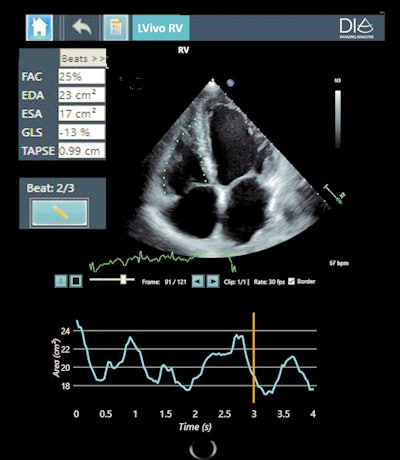

A number of other AI developers are targeting the market for cardiac image analysis. One firm has developed AI-based software that chooses the best cardiac ultrasound views from standard echocardiogram exams (LVivo Seamless, DiA Imaging Analysis). The company also offers applications for automated analysis of the heart's right ventricle (LVivo RV), as well as for automated bladder-volume measurements (LVivo Bladder).